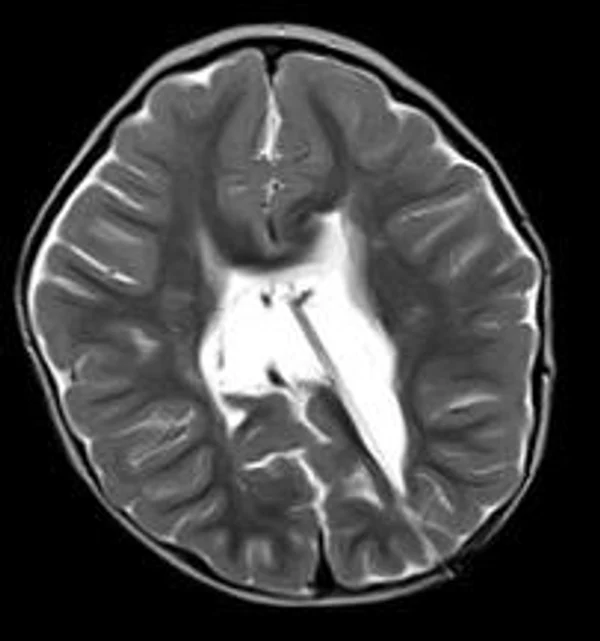

кисты, аномалии Денди-Уокера и др.Операции при внутричерепных кистах. В основном встречаются арахноидальные кисты различных локализаций и кисты сосудистых сплетений боковых желудочков. Пациентам с врождёнными кистами операции проводятся в следующих ситуациях: увеличении объема кисты в динамике, наличии клинических проявлений, компрессии и дислокации мозговых структур, наличии окклюзии ликворных путей. Нами используются 2 способа хирургического лечения кист: эндоскопическая перфорация стенок кист и открытая резекция кист. Открытая резекция кист проводится при ретроцеребеллярных арахноидальных кистах (рис. 2), при арахноидальных кистах межполушарной щели при отсутствии непосредственного контакта их стенок со стенками расширенных желудочков головного мозга и повторного увеличения кист средней черепной ямки после эндоскопической кисто-цистерностомии. Техника операции заключается в проведение краниотомии и максимальном иссечении стенок кист с созданием широкого сообщения кист с субарахноидальным пространством. Эндоскопические операции проводятся при арахноидальных кистах межножковой и пинеальной цистерн, арахноидальных кистах межполушарной щели при тесном контакте их стенок со стенками расширенной желудочковой системы (рис. 3), первично при арахноидальных кистах средней черепной ямки, а также при кистах сосудистых сплетений боковых желудочков. При арахноидальных кистах межножковой цистерны эндоскопически проводится перфорация стенок кисты, сообщая ее с просветом III желудочка и межножковой цистерной – эндоскопическая вентрикуло-кисто-цистерностомия (рис. 4). При арахноидальных кистах пинеальной цистерны проводится перфорация кисты в передне-верхних её отделах с созданием сообщения полости кисты с просветом III желудочка – эндоскопическая кисто-вентрикулостомия. С целью предотвращения облитерации сформированного отверстия иногда в полость кисты под контролем эндоскопа вводится стент перфорированный на протяжении (рис. 5, 6). Эндоскопическая кисто-цистерностомия выполняется при арахноидальных кистах средней черепной ямки. При этом создается широкое сообщение кисты с базальными цистернами. При кистах сосудистых сплетений боковых желудочков проводится их вскрытие в просвет боковых желудочков – эндоскопическая кисто-вентрикулостомия. При множественных кистах проводится их хирургическое сообщение между собой – интеркистосмия